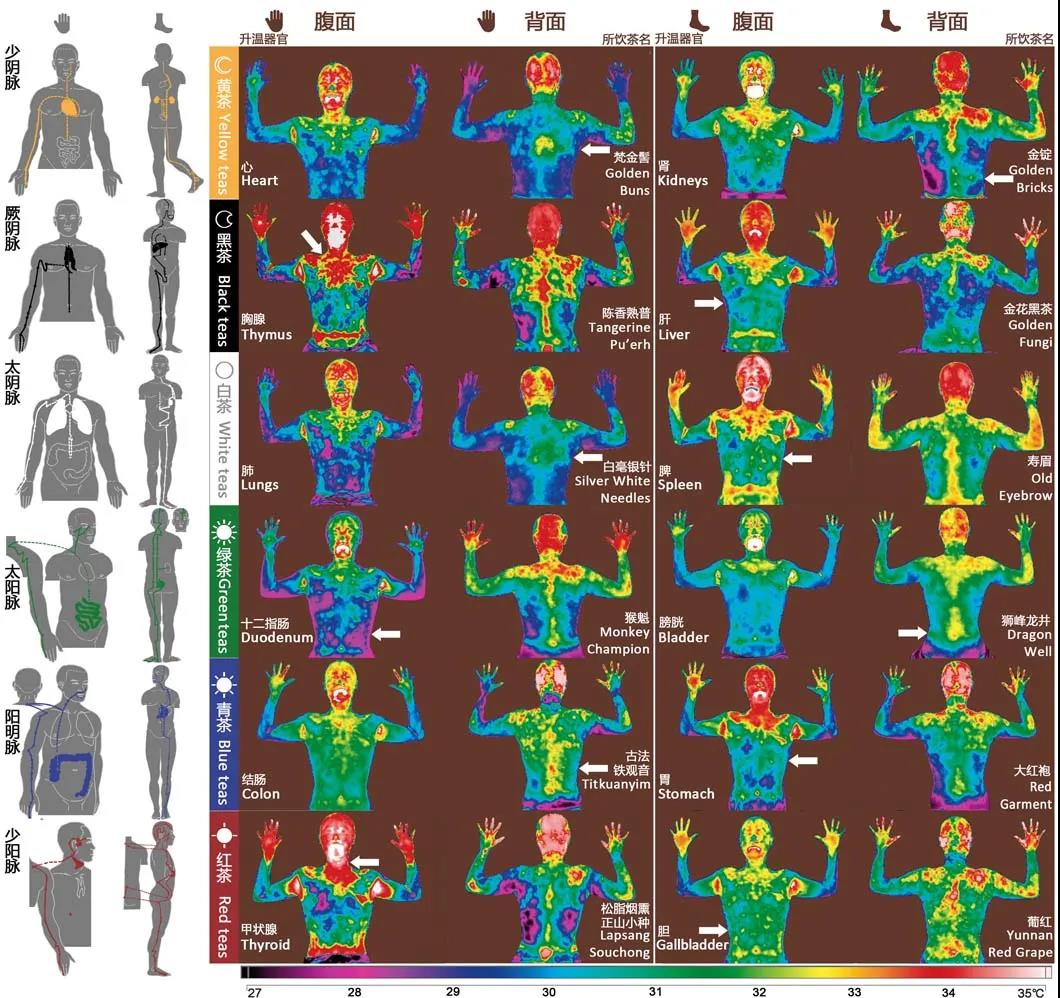

在饮用68种茶以后,研究团队做了一个结果统计,所有志愿者报告的一致性达到了96%。不同茶叶对应的归经有着极其明显的规律,绿茶对应太阳脉,青茶对应阳明脉,红茶对应少阳脉,白茶对应太阴脉,黑茶对应厥阴脉,只有黄茶并不清晰。

2017年,研究人员在贵州梵净山一带找到了含黄酮醇高的茶树,并发现以此生产出的黄茶对应少阴脉。

此后,研究团队从中国南方各省份以及印度、斯里兰卡、日本、美国、新西兰等国收集了512种茶,让人饮用之后,拍摄其身体的红外影像,观察红外辐射发生的时间和方式。其中一些茶喝了以后有强烈的经络流动感,仪器检测发现红外辐射会使体表产生5~8摄氏度的温差,核磁共振也看到细胞间质中大量液体流动。研究团队总结出最有效的茶叶激发的身体红外辐射影像,结果与2012年志愿者双盲测试的结果完全一样。

这种红外辐射在喝茶后的几秒钟内就会激发,但往往不会整条经络同时激发,而是分段地显现。只有极其特殊的情况下,归经效应特别强的茶种才能让整条经络几乎同时发出红外辐射。